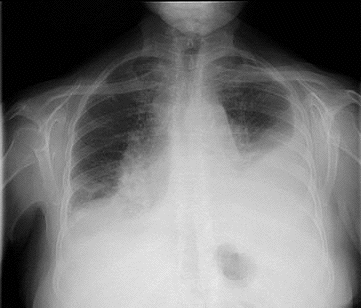

胸部CTでは、胸膜腫瘍[胸膜転移(胸膜播種、癌性胸膜炎、癌性胸水)]と同側の胸水貯留(癌性胸水)を認めます。重度の甲状腺機能低下症があれば、粘液水腫による胸水も考えねばなりませんが、その場合、胸膜腫瘍(胸膜播種)は無く、甲状腺ホルモンが正常化すれば胸水も消失します。

胸膜転移(胸膜播種、癌性胸膜炎、癌性胸水)では、胸部打診で濁音を示し、呼吸音が弱くなり、聴診で胸膜摩擦音が聞かれます。